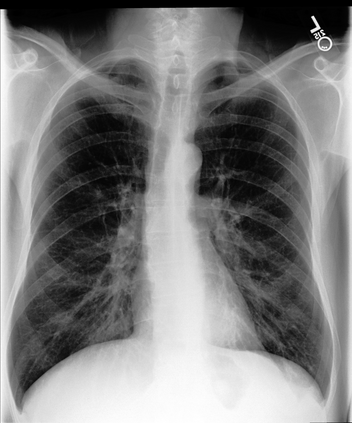

The latest breakthroughs in large vision-language models, such as Bard and GPT-4, have showcased extraordinary abilities in performing a wide range of tasks. Such models are trained on massive datasets comprising billions of public image-text pairs with diverse tasks. However, their performance on task-specific domains, such as radiology, is still under-investigated and potentially limited due to a lack of sophistication in understanding biomedical images. On the other hand, conversational medical models have exhibited remarkable success but have mainly focused on text-based analysis. In this paper, we introduce XrayGPT, a novel conversational medical vision-language model that can analyze and answer open-ended questions about chest radiographs. Specifically, we align both medical visual encoder (MedClip) with a fine-tuned large language model (Vicuna), using a simple linear transformation. This alignment enables our model to possess exceptional visual conversation abilities, grounded in a deep understanding of radiographs and medical domain knowledge. To enhance the performance of LLMs in the medical context, we generate ~217k interactive and high-quality summaries from free-text radiology reports. These summaries serve to enhance the performance of LLMs through the fine-tuning process. Our approach opens up new avenues the research for advancing the automated analysis of chest radiographs. Our open-source demos, models, and instruction sets are available at: https://github.com/mbzuai-oryx/XrayGPT.